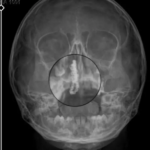

Kalın bağırsak kanseri riskinin bazı faktörlere bağlı olarak arttığını belirten Op. Dr. Hüseyin, “Özellikle 50 yaş üstü bireyler için düzenli tarama programları hayati önem taşımaktadır. 50 yaş ve üzerindeki bireyler, ailesinde kanser öyküsü bulunanlar, aşırı kırmızı et ve işlenmiş gıda tüketenler ile hareketsiz yaşam sürenlerin risk grubunda yer almaktadır. Hastalık erken dönemde belirti vermeyebilir ancak dışkılama alışkanlıklarında değişiklik, dışkıda kan görülmesi, karın ağrısı, şişkinlik, açıklanamayan kilo kaybı ve halsizlik gibi şikayetler dikkate alınmalıdır. Türkiye’de Sağlık Bakanlığı tarafından yürütülen tarama programları hastalığın erken teşhisinde önemli rol oynamaktadır. 50-70 yaş arasındaki bireylerin iki yılda bir gaitada gizli kan testi yaptırması önerilir. Kolonoskopi ise bağırsakların detaylı incelenmesini sağlar ve riskli poliplerin kansere dönüşmeden tespit edilmesine imkan tanır. Bu yöntemin 10 yılda bir uygulanması tavsiye edilir” dedi.